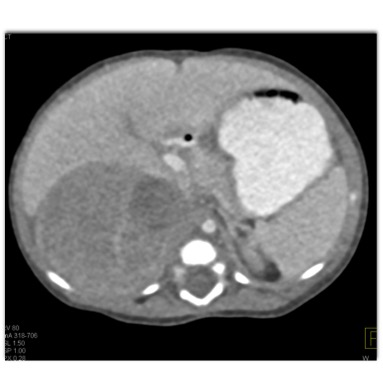

The best diagnosis in this 4 month old is?

Wilms tumor

adrenal hematoma

adrenal carcinoma

Neuroblastoma